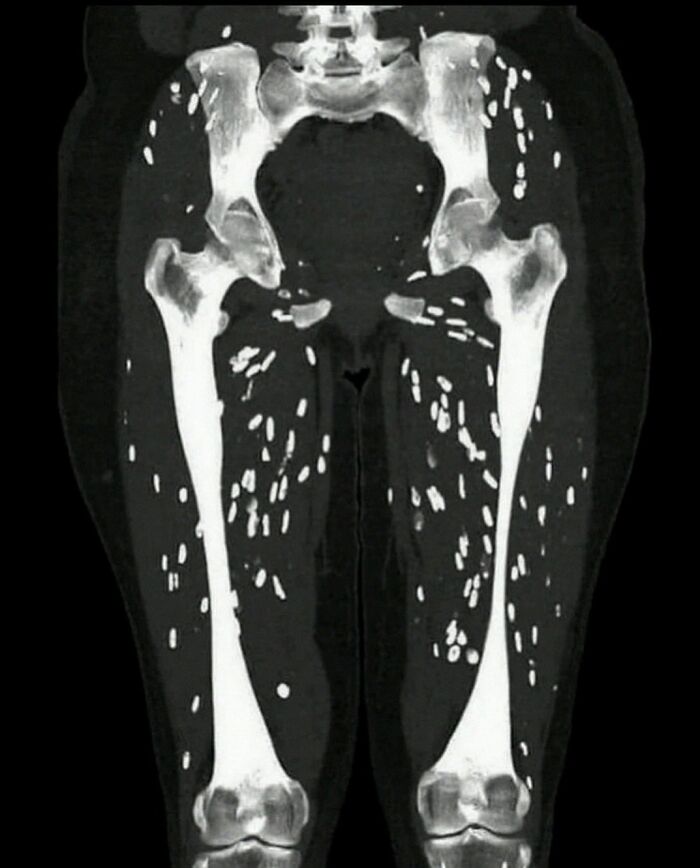

Patient presents with muscle weakness and pain

It's called muscular cysticercosis. Those are from tapeworm larvae in the muscle tissue. 😫😫